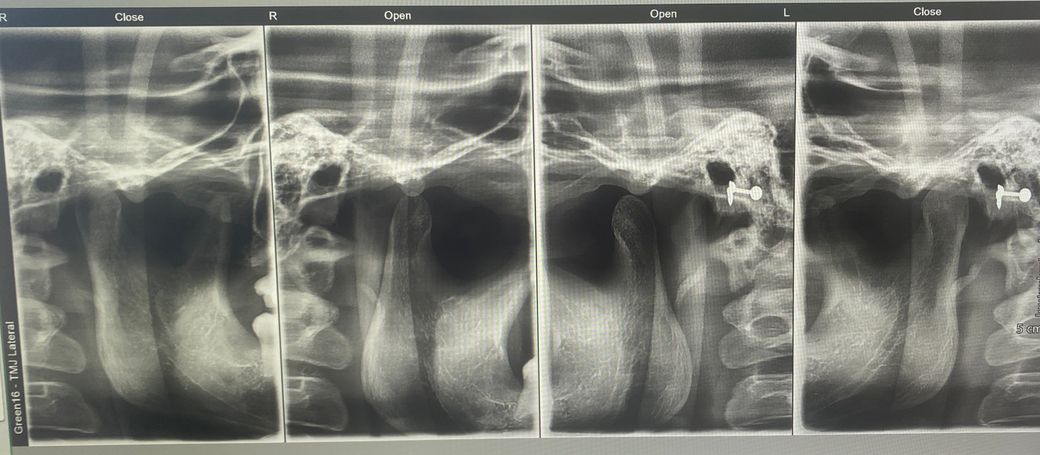

턱관절 엑스레이 상 과두 위치에 문제가 있을까요?

제 턱관절 엑스레이인데 엑스레이만 봤을 때 문제가 있어보이나요? 과두 위치가 정상적인지, 관절염이나 다른 이상소견이 있는지 궁금합니다

• 2번 째 사진

엑스레이 상으로 보면 턱관절 연골이 닳아잇는것처럼 보입니다. 통증이 잇거나 불편하시면 치과를 다니시면서 치료를 받아보시는게 좋을것같습니다.

과두위치 이상이나 관절염이 현재 올려주신 엑스레이 에서는 특정되어 나타나진 않습니다.

파노라마 사진상으로는 정확한 과두의 위치나 형태를 진단하기 어렵습니다.

턱관절 질환의 유무나 형태은 주로 증상이나 CT상으로 확인을 할수 있습니다.